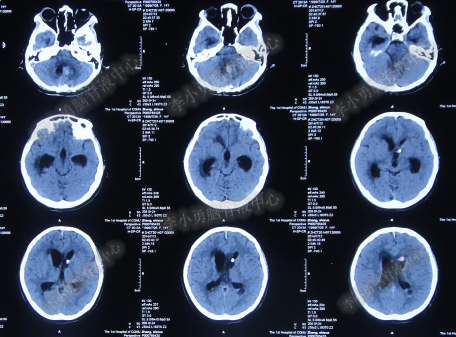

入院19天即2014年9月18日,病情进一步改善为:意识变清楚,双上肢能遵嘱活动,自主动作明显增多(图-35),头部CT示脑室缩小(图-36)。

图-35:2014年9月18日双上肢能遵嘱活动

图-36:2014年9月18日头部CT

入院治疗39天即2014年10月8日,查头CT示脑室缩小,右额叶见囊状含气密度,可见气液平面(图-37)。李小勇医生指示:目前CT显示颅内积气,存在原右额头皮切口愈合不良表现,给予切口清创缝合术。

图-37:2014年10月8日头部CT有积气